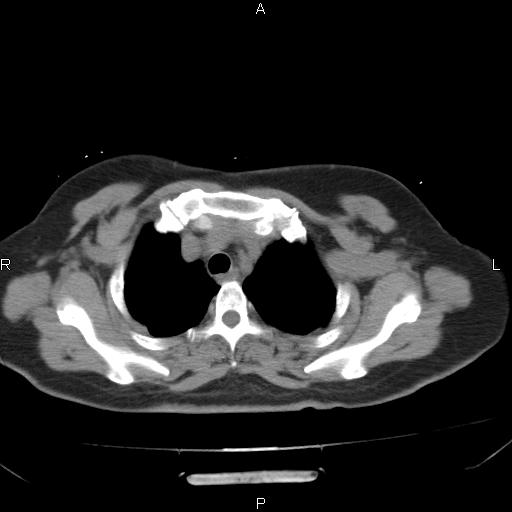

胸腺瘤

女、63Y 双眼睑下垂,早轻晚重。 胸腺瘤???

结果胸腺瘤